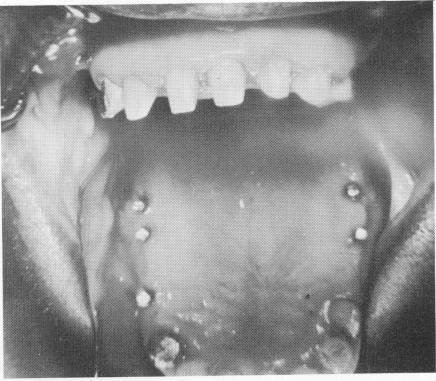

Roentgenograms and examination illustrated that all of the implants were firmly fixed deeply into the osseous tissue and that there were no pathologic areas (Fig. 4-19). There was no pain on palpation. Although the patient was completely comfortable, his implants were to be removed. Here was an ideal case for bone sections. After carefully removing the bridges, the tissues around the implants were found to be firm, healthy, and closely adapted to the implants (Fig. 4-20). The implants were removed by disking and cutting away part of the surrounding alveolar bone (Fig. 4-21) .

Fig. 4-20. Clinical view with the bridge removed. Note the healthy tissues under the pontics around the implant posts.

1 Healthy tissues under pontics around Chercheve`s spiral-post implants